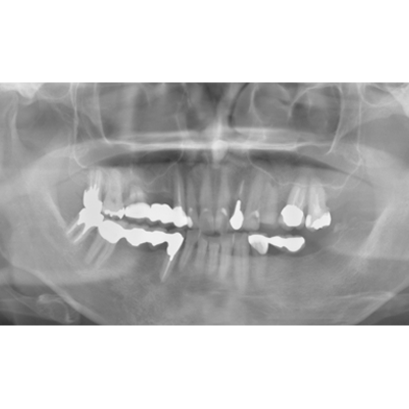

↑2006年4月24日

↑2006年4月24日(初診時)